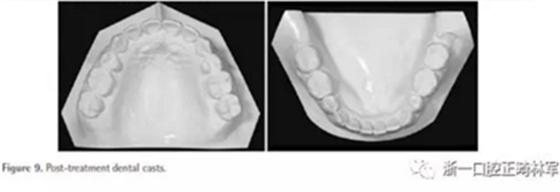

治療后面部和口內(nèi)照片顯示治療結(jié)果很成功(Figure 8)?;颊叩拿嫘瞳@得了非常顯著的改善,尤其是在唇部區(qū)域。覆合從-3.5mm增大到3.5mm,覆蓋從1.2mm增大到2.0mm。獲得了I類磨牙關(guān)系,沒有擁擠(Figures8 and 9)。

全景片顯示上前牙區(qū)未發(fā)生進(jìn)行性牙根吸收。然而,在下磨牙區(qū)有輕度牙根吸收,并且牙根平行性有改善空間(Figure 10A)。